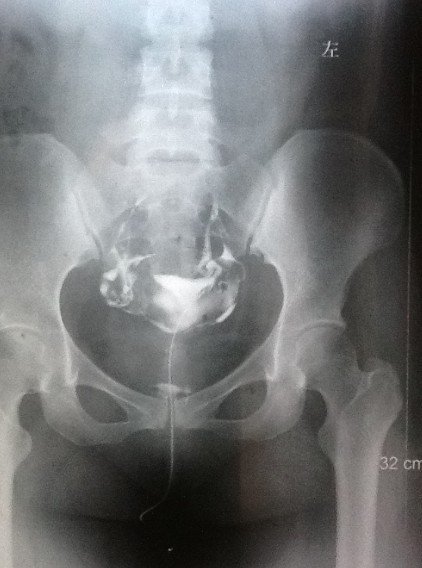

求助:帮我看看输卵管造影片吧

造影剂注入前 造影剂推入十几毫升时  造影剂完全推入  20分钟后的弥散照。 诊断:1.右输卵管炎          2.宫腔粘连         3.盆腔粘连给医生看了后,说我宫腔粘连不明显,有一小缺口可能是气囊,并配了妇炎康复胶囊和妇康消炎栓,治疗炎症。主要还是说盆腔粘连比较严重,需要宫腹腔镜。本人曾有过阑尾炎开刀史和胆囊炎开刀经历,对宫腹腔镜很是畏惧。请专家帮我看看,我的盆腔粘连是不是很严重。不做宫腹腔镜是否还有怀孕机会?